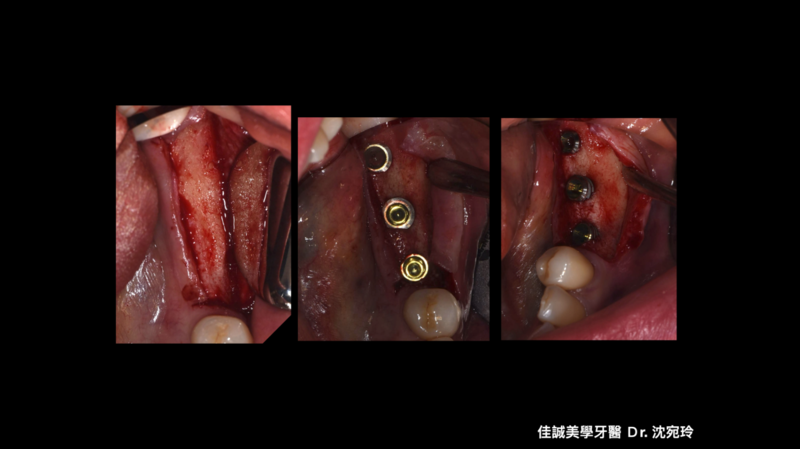

治療的開始是我們幫病患解決了疼痛,從病患腫痛,拆假牙、拔牙,恰好左下第一小臼齒為根管難症,仰賴錢正原醫師的成功顯微根管治療,取的病患的信任。接著我們一步步的重建,也因為這區是長達十幾年的五單位牙橋,拆掉後除了病患明顯左邊不好咀嚼,因此對於重建有強烈的企圖心,另外我們也看到因為長久缺牙而有牙脊萎縮,並伴隨角質化上皮缺損。缺損的骨頭部分我們是補得回來的,但一次三顆植體加上水平補骨,若在缺角質化上皮的這區手術,總覺得風險高了些。因為若有足夠的角質化上皮,可以讓我們植牙手術補骨縫合時,將縫線進針在角質化上皮內,縫線與角質化上皮內就像釘書針扎實的釘錨著,能對抗術後腫脹期防止傷口裂開,讓手術更能保證成功; 另外,若於其後補上骨粉和再生膜後,牙脊上的角質化上皮也相對穩定,不會在咀嚼時移動,讓其下方的骨粉可以好好轉換成自體骨; 角質化上皮的功能不只如上,在將來植體接假牙出來後,在咀嚼時,也因有足夠角質化上皮的包覆,能防止食物掉入和植體相接的牙肉內,防止植體周圍炎的產生。談到植體周圍炎的預防,植體植入的位置,最好平行假牙咬合軸向的受力,並且出孔位置在假牙的正中心。

以這個案例,我們量測了牙脊缺牙區的總寬度,再精算植體間距和植體寬度,後牙區小臼齒種植寬度長度4 mm X 11.5mm的植體,大臼齒則置入兩支寬度長度5 mmX11.5mm的植體,而在設計時在軟體內要讓三顆植體盡可能平行,以利將來植牙贋復製作,減少應力集中造成植體周圍炎的可能。我們利用模子的STL檔和斷層掃描的DICOM檔做疊合,在Bluesky軟體內,由醫師自己設計出最佳的植體位置、寬度長度,再請專業的3D列印公司做數位模板輸出。因為在軟體內我們已經看出將來植體的位置和需補骨的量,進而反推切線的位置,最後我們知道角質化上皮終究都需要補一場,於是治療計畫一開始就是先補上角質化上皮,等四個月後軟組織穩定,我們接著利用手術導板植入三個植體,並於當次補入骨粉和再生膜,術後如我們預期,傷口恢復良好。